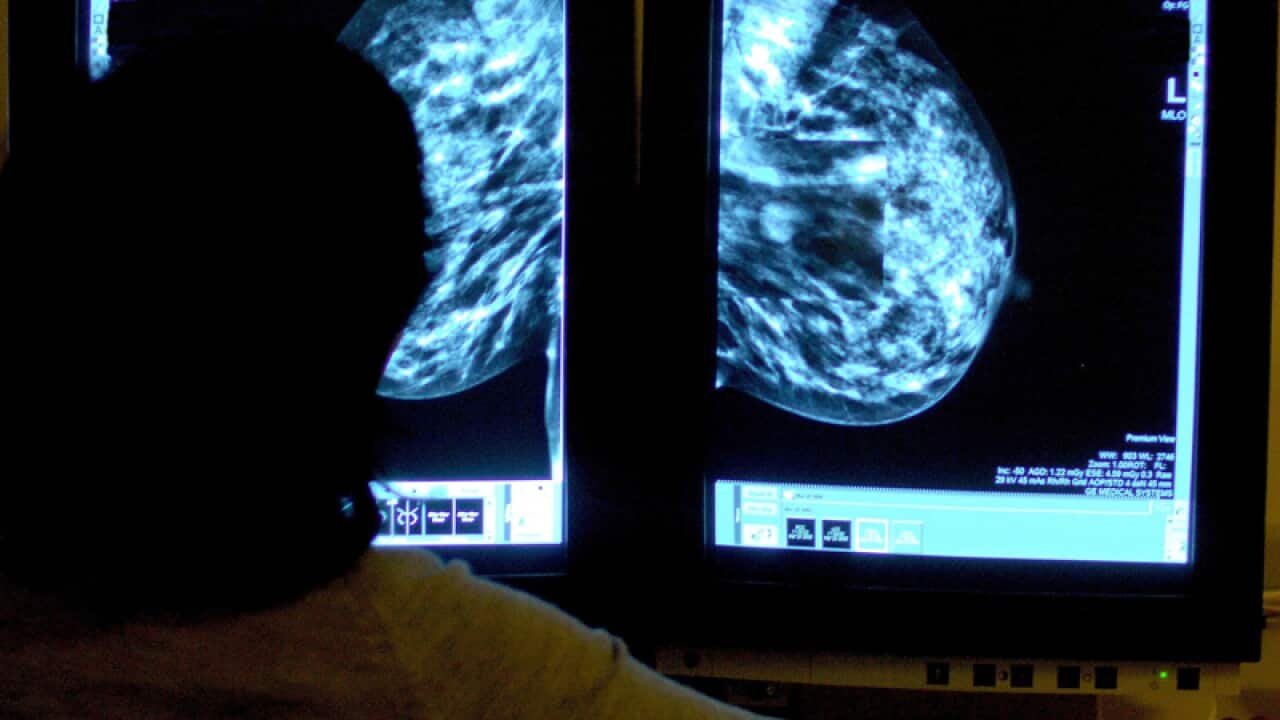

Bureau data shows that breast cancer is the 13th leading cause of death in Australia, with 3,004 deaths recorded in 2016.

Understanding why some women are more at risk of dying from breast cancer than others is the focus of a major research project launched by the National Breast Cancer Foundation.

While breast cancer has one of the highest survival rates at 90 per cent, there are hundreds of women who still die within five years of being diagnosed with the disease.

Eight women in Australia die of breast cancer every day, statistics show.

Researchers at the Centre for Population Health Research at the University of South Australia will pull together all the data from hospitals, radiotherapy centres and tissue banks to help answer the question: Why are 10 per cent of women still not surviving beyond five years?

"What's different about them and what can we do about it?" said Professor Ian Olver, a chief investigator on the project.

"If we can link all the data together, we can find out more about what puts people at greater risk of not doing well."

The research, announced on Wednesday at the launch of the Pink Ribbon Breakfast fundraising campaign, will start in SA and then broaden nationally.

Some of the questions to be asked will examine survival outcomes for women living in rural towns and younger women.

Prof Olver says he's "absolutely confident" of producing new data that will lead to tailored treatments and, ultimately, improved survival.

"What you do is look at the population to get your clues and then you can design very specific studies that will be able to translate into individual treatments, so you use the big data set and then you can design the studies then that are very specific to get answers for individual patients," Prof Olver told AAP.

NBCF CEO Professor Sarah Hosking says they will use the information to identify any gaps in care and what changes the health system needs to do to fill them.

"Over the past 20 years, research has come so far in reducing deaths from breast cancer, but until we reach zero deaths we believe the job's not done," she said.

"NBCF will use this information to make data-driven decisions in setting research priorities that are focused on closing the gap on the last 10 per cent of breast cancer deaths and making it a better tomorrow for those affected."